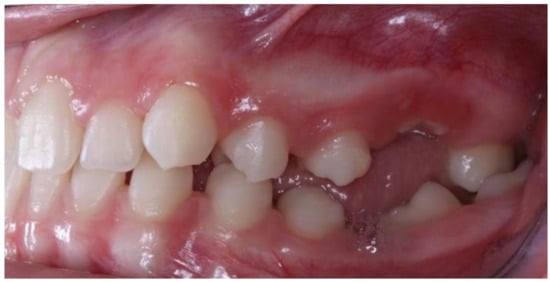

Figure 5.

Right photo of the female patient with PFE in bite relationship.

Figure 6.

Left photo of the same female patient depicted in Figure 5.

Open bite is present at the right posterior segment due to the impaction of the upper and lower left first molars.

Figure 5 and Figure 6 present a PFE case of a 17-year-old female patient referred to the Orthodontic Clinic of the Dental School of the National and Kapodistrian University of Athens, Greece. Clinical examination showed a posterior open bite on the right segment, as well as infraoccluded left upper and lower first molars. The patient’s orthopantomography shows no visible PDL of the right upper and lower first molars or the teeth distally related to them.